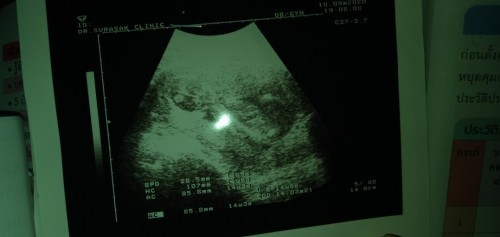

26 มีนาคม 64 ท้องแรกค่ะ นับวันรอทุกวันเลยเนาะแม่ อยากเห็นน่าลูกแล้ว อีกสองเดือนกว่า ปี64 เป็นปีที่ดีนะแม่ ปีฉลูทอง 60 ปีมีครั้ง ถือว่าลูกเรามีบุญมากที่เกิดปีนี้

บ้านนี้ 18 มีนา ท้องแรกค่ะ หนีบไว้ไม่ให้แม่เห็นเพศเลย